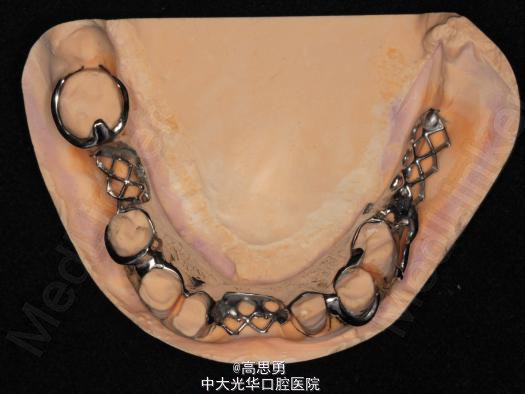

5、试戴支架 检查支架的就位、固位可,无翘动,调HE,抛光,用蜡堤取颌位关系,上颌架,排牙,比色C4。

对于肯氏II类上下牙列游离端缺损的病例,义齿的支持形式为基牙与黏膜共同支持式,由于基牙与黏膜的可让性不同,受力后义齿不同的部位产生的位移不一致,使得义齿在行使咀...查看全部

病历发表的很认真,很详细,双侧或者单侧游离缺失,传统三臂卡修复对基牙扭力很大,楼主这方面考虑的很周到,在游离端缺失都选择了RPA或者RPI卡环,改变义齿支持模式...查看全部